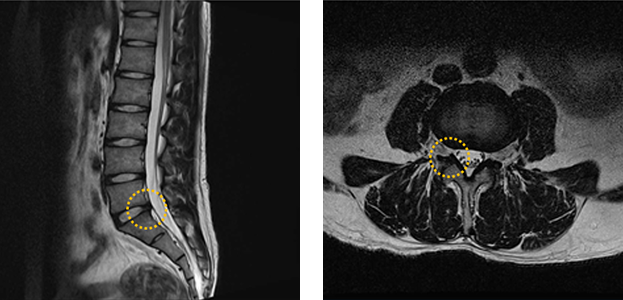

정상환자 MRI

• 측면 MRI

• 단면 MRI